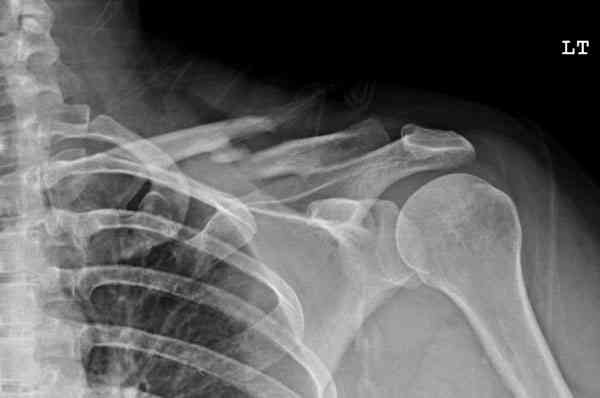

Второй случай тоже недавно оперирован по поводу

ложного сустава, в марте травма, через 4.5 половиной

операция..